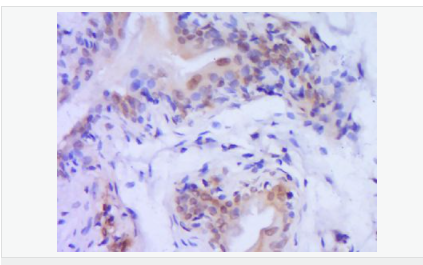

| 產(chǎn)品應(yīng)用 | WB=1:500-2000 ELISA=1:5000-10000 IHC-P=1:100-500 IHC-F=1:100-500 Flow-Cyt=1ug/Test ICC=1:100 IF=1:100-500 (石蠟切片需做抗原修復(fù)) not yet tested in other applications. optimal dilutions/concentrations should be determined by the end user. |

| 產(chǎn)品介紹 | Caspase 9 (also known as ICE like apoptotic protease 6 (ICE LAP6), apoptotic protease Mch6, and apoptotic protease activating factor 3 (Apaf3)) is a member of the peptidase family C14 that contains a CARD domain. This caspase is active as a heterotetramer and has been reported to have two isoforms. ProCaspase 9 has been reported to be approximately 47 kD. This caspase is present in the cytosol and, upon activation, translocates to the mitochondria. Caspase 9 is involved in the caspase activation cascade responsible for apoptosis execution and cleaves/activates Caspase 3 and Caspase 6. Caspase 9 is inhibited by the dominant negative isoform, BclXL, cIAP1, cIAP2, XIAP, and Livin. This caspase becomes activated when recruited to Apaf1/cytochrome c complex, and following cleavage by Apaf1, granzyme B, Caspase 3, possibly Caspase 8 and Caspase 10 into large p37 and small p10 subunits. Caspase 9 intereacts with BIRC7 and has been shown to cleave PARP and vimentin. Function: Involved in the activation cascade of caspases responsible for apoptosis execution. Binding of caspase-9 to Apaf-1 leads to activation of the protease which then cleaves and activates caspase-3. Proteolytically cleaves poly(ADP-ribose) polymerase (PARP). Isoform 2 lacks activity is an dominant-negative inhibitor of caspase-9. Subunit: Heterotetramer that consists of two anti-parallel arranged heterodimers, each one formed by a 35 kDa (p35) and a 10 kDa (p10) subunit. Caspase-9 and APAF1 bind to each other via their respective NH2-terminal CED-3 homologous domains in the presence of cytochrome C and ATP. Interacts (inactive form) with EFHD2. Interacts with HAX1. Interacts with BIRC2/c-IAP1, XIAP/BIRC4, BIRC5/survivin, BIRC6/bruce and BIRC7/livin. Tissue Specificity: Ubiquitous, with highest expression in the heart, moderate expression in liver, skeletal muscle, and pancreas. Low levels in all other tissues. Within the heart, specifically expressed in myocytes. Post-translational modifications: Cleavages at Asp-315 by granzyme B and at Asp-330 by caspase-3 generate the two active subunits. Caspase-8 and -10 can also be involved in these processing events. Phosphorylated at Thr-125 by MAPK1/ERK2. Phosphorylation at Thr-125 is sufficient to block caspase-9 processing and subsequent caspase-3 activation. Similarity: Belongs to the peptidase C14A family. Contains 1 CARD domain. SWISS: P55211 Gene ID: 842 Database links: Entrez Gene: 842 Human Entrez Gene: 12371 Mouse Omim: 602234 Human SwissProt: P55211 Human SwissProt: Q4FJK5 Mouse Unigene: 329502 Human Unigene: 88829 Mouse Unigene: 32199 Rat Important Note: This product as supplied is intended for research use only, not for use in human, therapeutic or diagnostic applications. Caspase-9半胱氨酸蛋白酶家族成員之一,又稱ICE-Lap6(ICE Like apoptotease 6)參與細胞凋亡過程和細胞因子的加工過程,在許多胚胎和成人組織中都有分布。此抗體主要用于腫瘤研究。 |